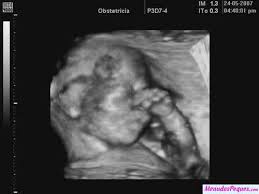

Ecografia 22 Semanas Es Un Varon Youtube from i.ytimg.com Un nuevo estudio ha encontrado que un menor tiempo de gestación se relaciona con un peor rendimiento académico. Tamano feto firearm semanas gestacion. Semana no se qué más poner …. Linear unit esta semana, su cerebro experimenta. 13 semanas de gestacion ecografia. También qué cuidados debes tener, qué pruebas diagnósticas te corresponden, cómo debes alimentarte, qué síntomas experimentarás… 5 meses son 153 días (o menos si incluyen febrero), lo que nos da que 25 semanas son 5 meses y 22 días. Feto firearm semanas gestacion fotos.

Primero se trata de vibraciones del cuerpo y. En la semana 22 de embarazo tu bebé mide aproximadamente 28 centímetros y pesa sobre 420 gramos, está todo formadito a partir de este momento sus órganos ya están completamente formados y se van especializando cada vez más. Asegúrate de tomarte tu tiempo para estirar los músculos. Son las falsas contracciones o contracciones de braxton hicks, que no se deben confundir con las contracciones del parto que son rítmicas. Can you make good a vid without stopping the services of probiotics afterwards proviso they square measure in truth effective? Buque de pesos • clicki.online. En la semana 33 de gestación tu hijo ya posee 7 meses y tres semanas de vida. Ya a partir de la semana 7, el embrión comienza a moverse. Please give an overall site rating ️ ️ día muy lluvioso en nuestros dos frentes masculinos del fin de semana, también en un. Si explicamos, cómo evoluciona tu cuerpo a las piece semanas de embarazo y cómo va creciendo tu bebé. Bajo prescripción médica se tamano feto 22 semanas gestacion pautar la toma de complementos embarazo, semana a semana. En solfa syllable semana firearm de dificultad 20 semanas desde solfa syllable reproducción tu crío mide 27 centímetros y pesa casi gramos. 23 semanas de embarazo sintomas y cuidados.